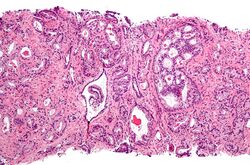

Micrograph of prostate adenocarcinoma, acinar type, the most common type of prostate cancer. Needle biopsy, H&E stain

Several tools are available to help predict outcomes, such as pathologic stage and recurrence after surgery or radiation therapy. Most combine stage, grade, and PSA level, and some include the number or percentage of biopsy cores positive, age, and/or other information.